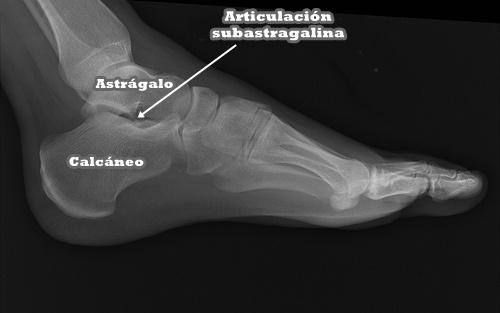

Se pueden apreciar cambios degenerativos en la articulación subastragalina. La adquisición de pie plano, va a llevar a un mal funcionamiento de esta articulación y su consequente deterioro.

Articulación subastragalina